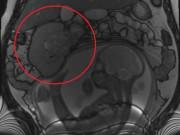

Ngày phẫu thuật, chính bác sĩ cầm dao mổ cũng phải bất ngờ khi lấy ra từ bụng cô Trương một khối u khoảng hơn 7kg, đường kính 30cm. Bên ngoài khối u là thịt, bên trong là dịch và còn lẫn cả răng và tóc.

Các bác sĩ cho biết khôi u này là một u nang bì buồng trứng hay còn gọi là u quái. Khối u có chứa các mô tuyến bã, da, tóc, xương,… Đặc biệt hơn, bản chất của khối u này chính là tế bào mầm của phôi thai, biệt hoá thành xương răng, tóc...